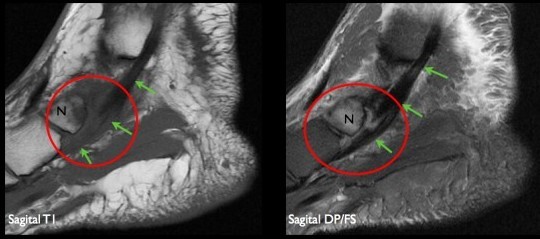

△ 후경골근건(초록색 화살표)의 거대화와 주상골(N)의 골수종

△ 정상적인 장지굴근건(노란색 화살표)과 장모지굴근건(분홍색 화살표)